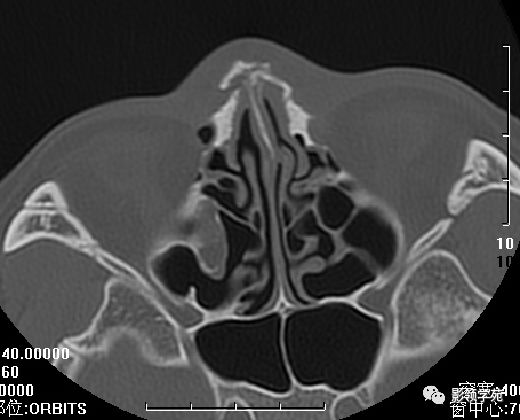

鼻骨横断面HRCT

双侧鼻骨骨折

鼻中隔骨折